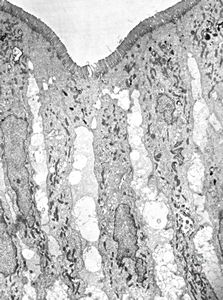

M,35y. | duodenum … lipid malabsorption - susp. hypo-beta-lipoproteinemia